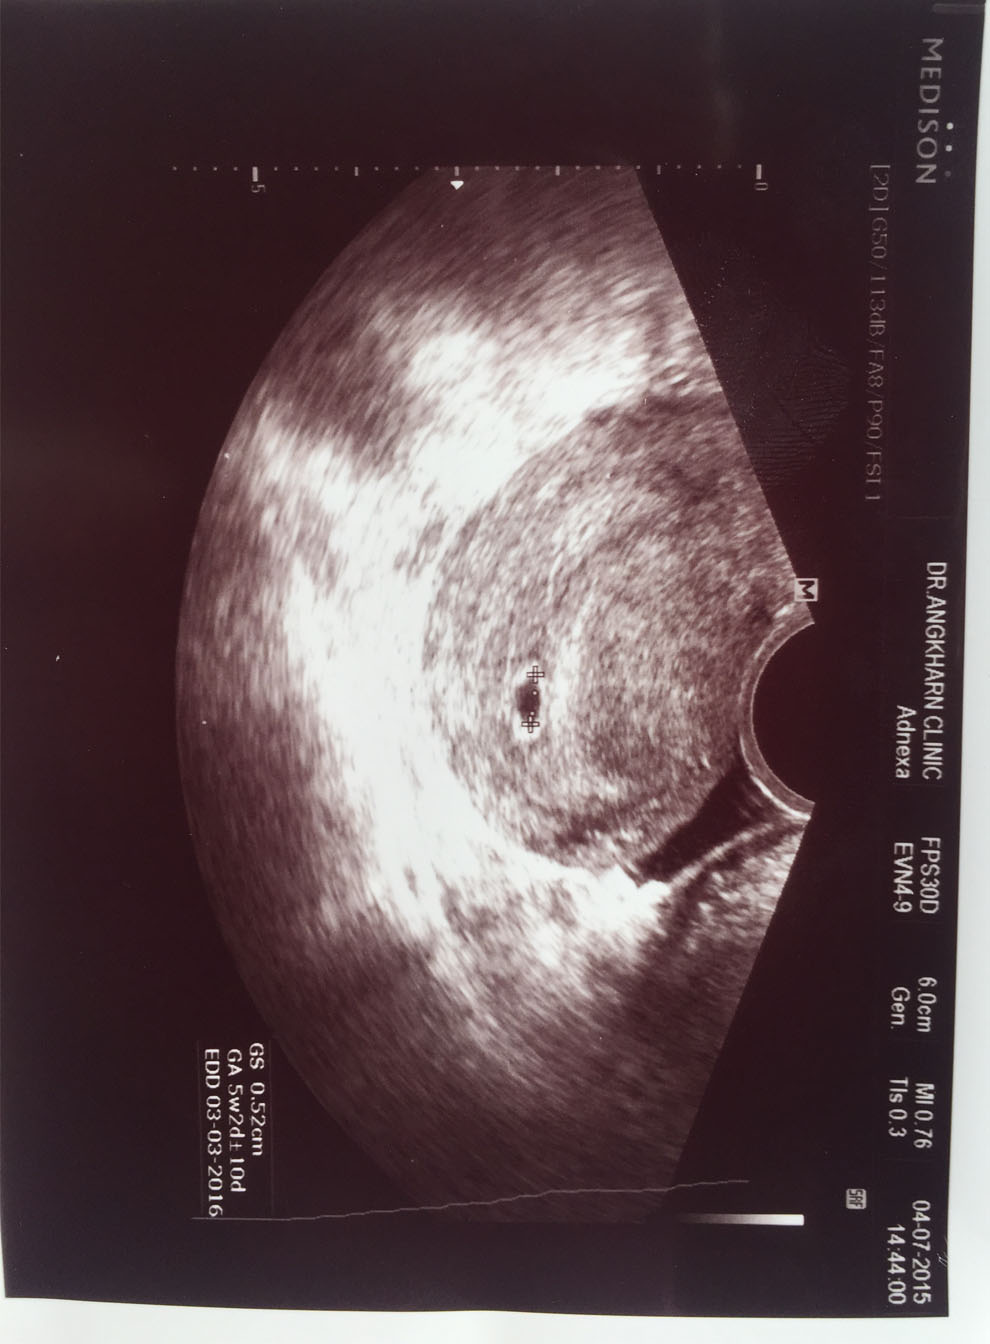

วันต่อมาออฟบอกเอวาจะมากินข้าวเที่ยงด้วย แต่ความจริงออฟพาไปตรวจที่คลิดนิกแห่งหนึ่งหาอายุครรภ์จริงๆ และผลก็ออกมาเหมือนเดิม หาไม่เจอเพราะอายุครรภ์น้อยมาก และเอจึงบอกออฟว่า ถ้าเอหาหลักฐานว่าท้องแค่สามสัปดาห์จริงๆ แฟนออฟจะยอมหยุดใช่ไหม หยุดวุ่นวายกับเอ และเอก็สามารถตรวจหาอายุครรภ์จริงๆ มีคลินิกที่หนึ่งที่สามารถตรวจได้โดยการส่องเจ้าไปในช่องคลอด และผลออกมาคือ 5 สัปดาห์ 2 วัน

รู้ไหม วินาทีที่ส่องเห็นก้อนดำๆมันเป็นอะไรที่พิเศษมาก มันคือลูกของเอ เอบอกหมอระวังนะคะ เอกลัวลูกหลุด และบอกตัวเองว่าเอจะรักษาลุกให้ดีที่สุด และเอก็เอาแผ่นอัลตร้าซาวไปให้ออฟ และบอกออฟว่าเอขอให้ทุกอย่างจบนะ ออฟรับปากว่ามันจะจบ